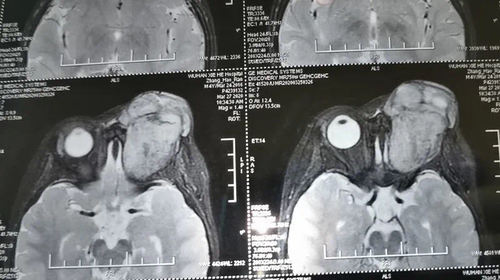

孩子4个月前有过一次眼部碰伤,在当地医院CT检查诊断为眶内血肿,先后两次抽出眶内积血,但是每次都稍有缓解,不久后就会复发。后来因为新冠肺炎疫情和武汉封城,没能及时就诊。这时,孩子的眼球突出已经非常严重,眼球全部突出于眼眶外,角膜暴露,视力丧失,由于极度的眶压升高十分痛苦,患儿哭闹不止。

经过快速、仔细的检查和阅片,孙丰源做出明确诊断:眼部恶性肿瘤!因持续高眶压和角膜暴露,孩子已经数日不能正常饮食,情况非常危险,而肿瘤也在快速增长。为挽救孩子的生命应紧急手术!